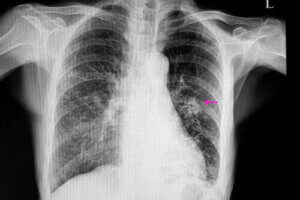

I sådanne tilfælde, vil knuden have et uregelmæssigt udseende med uklare kanter. Det er synligt på et røntgen. De er som regel også mindre end de godartede. Derudover er de en del af bestemte risikofaktorer, såsom:

Når dette er gjort, skal en læge udføre bestemte billeddannelsestests for at kunne afgøre knudens placering. Derudover, vil billederne give dem mulighed for at observere bestemte karaktertræk såsom form og størrelse. Det skyldes, at de er vigtige for at kunne differentiere en godartet knude fra en mulig ondartet en.

De mest gængse metoder til at diagnosticere dem er via røntgen af lungerne og CT-scanninger. For at kunne finde ud af den præcise årsag til en knude i lungerne, udfører læger også nogle gange biopsier, eftersom de giver mulighed for at analysere vævene.